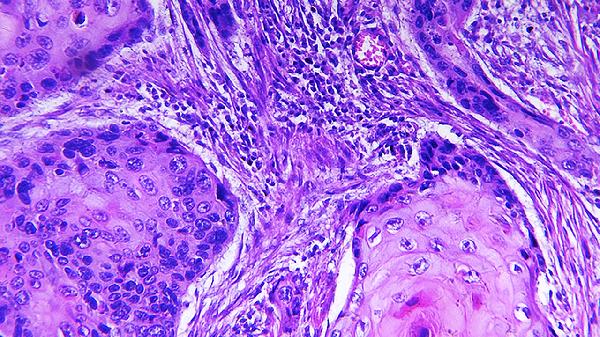

2.神经内分泌癌属于高度恶性肿瘤,生长迅速,易发生远处转移,常见于肺部、胰腺和胃肠道。病理检查显示细胞分化差,Ki-67指数较高,侵袭性强。治疗方法包括手术切除、化疗(如顺铂联合依托泊苷)和靶向治疗(如奥曲肽),晚期患者可考虑放射性核素治疗或免疫治疗,术后需密切随访。

3.神经内分泌瘤和神经内分泌癌的诊断需结合病理学、影像学和临床表现。病理检查通过免疫组化染色(如嗜铬粒蛋白A、突触素)和Ki-67指数评估肿瘤性质,影像学检查(如CT、MRI、PET-CT)评估肿瘤位置、大小和转移情况。早期诊断和规范化治疗对改善预后至关重要。